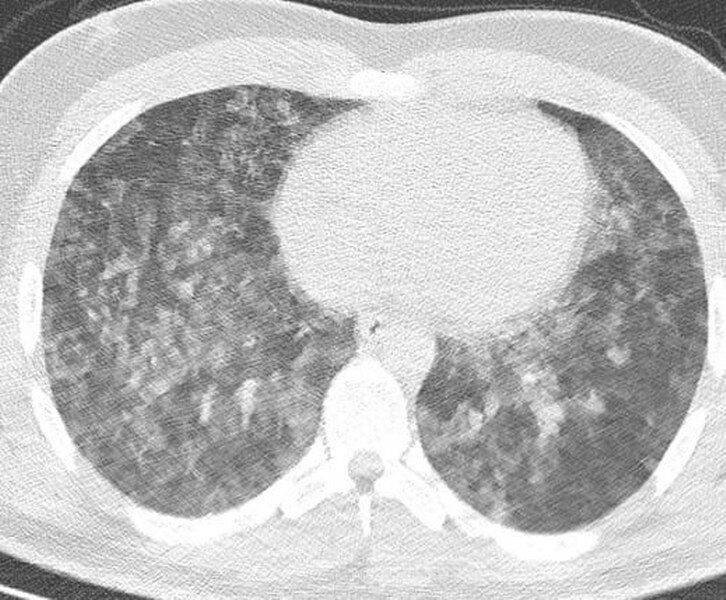

21 yaşındaki bir gencin tomografisini örnek olarak paylaşan Özkaya, "Tokat’tan gelen 21 yaşındaki bir vatandaşımız Samsun’da ciddi bir boğulma tehlikesi geçirdi. Canlandırma müdahalesiyle yoğun bakımda takip edilerek hayata tutundu ve sağlıklı şekilde taburcu edildi" dedi.